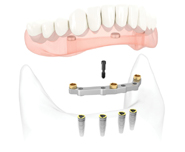

DenturesOver Dentures